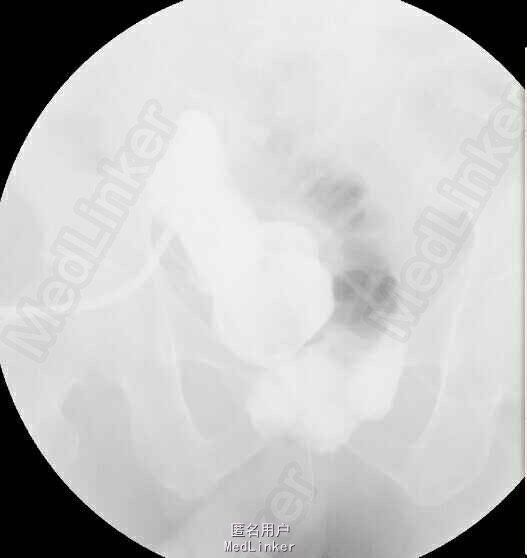

术后病理示:(膀胱肿物)形态学可符合高级别尿路上皮癌,鉴于送检组织表浅且破碎,并于2015-xx全麻下行“腹腔镜根治性膀胱切除术+原位回肠新膀胱术”,腹腔镜下根治性切除膀胱并行双侧盆腔淋巴结清扫,并行回肠原位新膀胱,术后恢复满意,各管道引流通畅,术后病理示:(膀胱肿物)高级别浸润性尿路上皮癌,癌组织浸润粘膜固有层,盆腔淋巴结均未见癌转移。术后复查膀胱造影示:代膀胱充盈良好;代膀胱-尿道吻合口处少许造影剂。拟带管出院。患者术后恢复良好无发热,腹胀、腹痛,饮食、睡眠正常。留置右肾单J管、膀胱造瘘管、左侧盆腔引流管及尿管引流通畅。